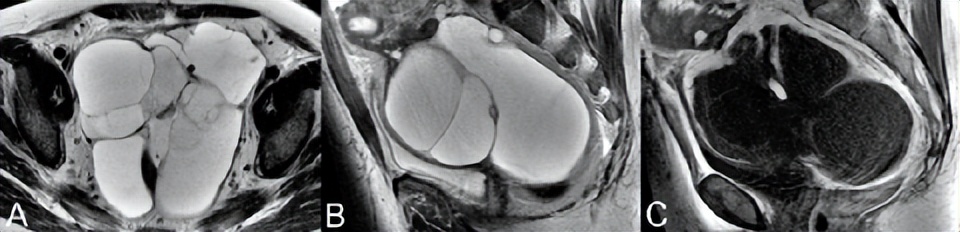

功能性滤泡性卵巢囊肿是常见的良性病变,通常表现为单房、薄壁病变,伴有水样信号(图76.1,轴位T2WI)。无功能性囊性病变是鉴别诊断因素,但由于肿瘤形成可能看起来相似,因此应在6周内通过超声重新评估新诊断的30 mm以上卵泡囊肿。滤泡囊肿的囊壁增强不如黄体囊肿。后者的壁通常也较厚,如图76.2A的冠状T2WI(白色箭头)所示,(B) CE T1WI显示管壁明显增强。

出血性黄体囊肿很常见,在图76.2C中示出,在轴位(C,白色箭头)T1和(D) T2WI上D分别为高信号和低信号。多囊卵巢综合征(PCOS)和卵巢过度刺激综合征中可见多个双侧囊肿。在多囊卵巢综合征中,根据定义,此类囊肿小于10 mm,位于外周和包膜下,与突出的低信号中心间质相邻。在卵巢过度刺激综合征中,囊肿可能较大且为非外周性囊肿。对于后者,可能出现腹水和胸腔积液,同时扭转风险增加。

▲ 图76.2